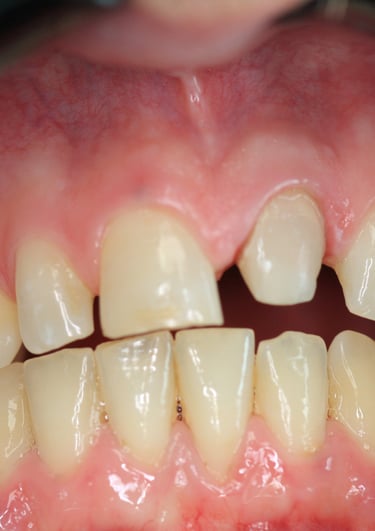

4. Prova Estetica e Cementazione della Corona Definitiva

La corona definitiva in disilicato di litio è stata progettata per mimetizzarsi perfettamente con i denti naturali in termini di colore, traslucenza e forma. Dopo una prova estetica accurata, la corona è stata cementata utilizzando un cemento adesivo di ultima generazione, garantendo un'adesione duratura e stabile

Corona Estetica

Condizioni Finali

La sostituzione della corona su un incisivo centrale richiede un approccio multidisciplinare che coniughi precisione clinica ed eccellenza estetica. In questo caso, il ritrattamento endodontico, la sostituzione del perno moncone e la realizzazione di una nuova corona in disilicato di litio hanno permesso di ottenere un risultato ottimale sia dal punto di vista funzionale che estetico.

Grazie all'impiego di materiali avanzati e tecniche minimamente invasive, è stato possibile garantire al paziente una riabilitazione duratura, ripristinando la stabilità protesica e l’armonia del sorriso. Questo caso conferma l'importanza di una diagnosi accurata e di un piano di trattamento personalizzato per risolvere definitivamente le problematiche legate alle corone incongrue.

Il successo del trattamento non si misura solo nella qualità della protesi finale, ma anche nella soddisfazione del paziente, che può ora sorridere con sicurezza e senza preoccupazioni.